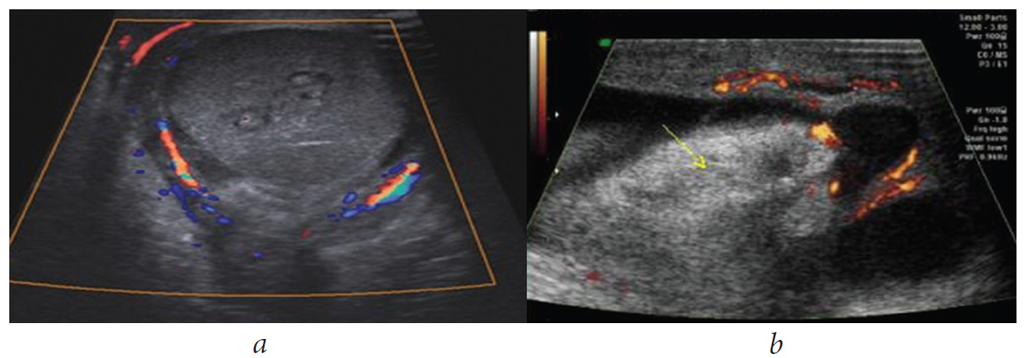

Time from the onset of testicular torsion was <6 h in 8 (22.2%) patients, 6–12 h in 10 (27.8%) patients, 12–24 h in 11 (30.6%) patients, and >24 h in 7 (19.4%) patients. Based on the scrotal Doppler US findings, no blood flow in the testicular artery and a sharp increase in testicle and epididymis size were observed in 28 patients. The other 8 patients showed decreased blood flow in the testicular artery and an increase in epididymis and testicle size (Fig. 2 and 3). In patients with time of onset of testicular torsion <6 h, the decrease in blood flow in the testicular artery was determined by scrotal Doppler US, and incomplete testicular torsion of 180° was observed during the revision of the scrotum. In this case, it was possible to save the testicle and fix it to the tunica of the septum and tunica dartos. In patients with time of onset >12 h, testicular torsion of 360° with insufficient blood flow in the testicular artery, destructive changes in the testicular tissues and epididymis, and signs of hydrocele were detected.

Fig. 2. Patient C., 30 years old. Scrotal Doppler ultrasound before surgery: a – normal blood flow in the right a.testicularis; b – absence of blood flow in the left a. testicularis, left testicle enlargement and torsion

Fig. 3. Patient B., 27 years old. Scrotal Doppler ultrasound before surgery: a – significant blood flow decrease in testicular blood vessels, congestion of testicular tunics, lythic lesion of testicular parenchyma; b – absence of pulsation below torsion